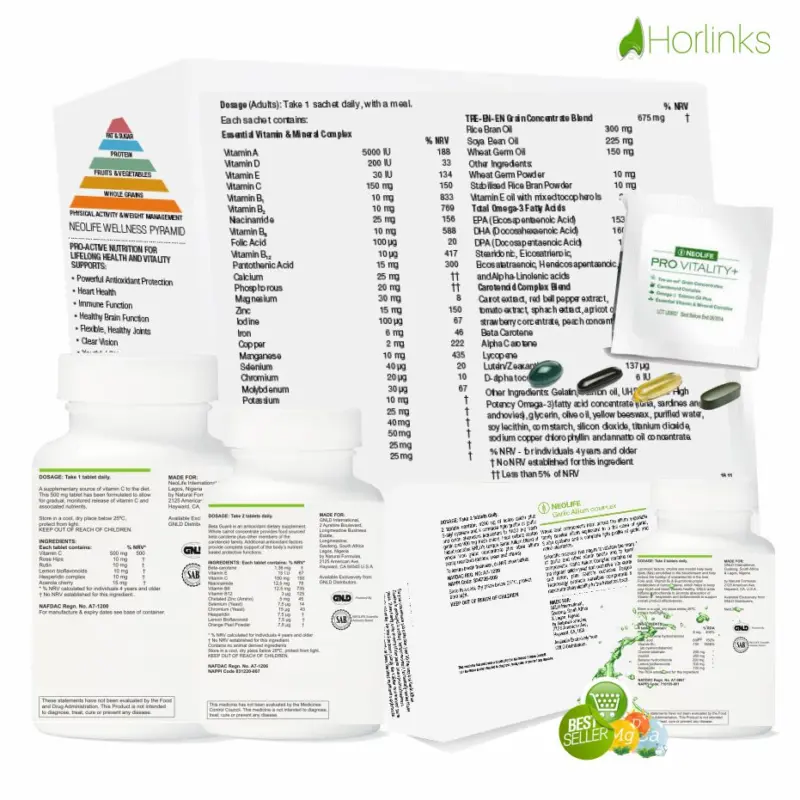

Quitting smoking is the most important way to protect your lungs, to help reduce inflammation in the airways. Doing this may relieve pressure on the breathing muscles and help improve lung elasticity (or stretch). Clinically, we recommend a conscious lifestyle and dietary changes immediately*! Also we urge you to take back your hearth health, helping your arteries metabolise promptly; with purification approach to re-balance your heartbeat functioning optimally with our Essential Nutritional Dietary Supplements by NEOLIFE;

1. Beta Guard in 100 Tablets; take 3 tablets daily.

2. Pro Vitality+ in 30 Sachets; take 1 sachet daily.

3. Vitamin C. Sustained Release in 100 Tablets; take 3 tablets daily.

4. Garlic Allium Complex in 60 Tablets; take 2 tablets daily.

5. Lipotropic Adjunct in 90 Tablets; take 3 tablets daily.

Each packet of Pro Vitality provides daily whole food nutrition for lifelong health and vitality from whole grains, fruits & vegetables, fish and vitamins & minerals*!

Powerful nutrients that support: Abundant Energy, Powerful Antioxidant Protection, Lifelong Heart Health, Optimum Immune Strength, Healthy Brain Function, Flexible, Healthy Joints, Clear Vision, Youthful Skin, Hair and Nails, Lifelong Cellular Health and Natural Genetic Anti-Aging Function

• Tre-en-en® Grain Concentrates

FEED YOUR CELLS – ENHANCE YOUR ENERGY The world’s first and only whole grain lipid and sterol supplement proven to enhance your energy and vitality by optimizing cellular nutrition. A study conducted at Texas A&M University showed it improved nutrient utilization efficiency*!

• Carotenoid Complex™

PROTECT YOUR CELLS – OPTIMIZE YOUR IMMUNITY The world’s first and only whole food supplement clinically proven by USDA researchers to protect heart health, and boost immune function. It provides the protective power of carotenoids from whole fruits and vegetables. A high potency formulation of broad-spectrum carotenoids—so unique we patented it!

• Salmon Oil Plus™

BALANCE YOUR CELLS – MAXIMIZE GOOD HEALTH Clinically proven to support heart and cardiovascular health, and to lower inflammatory index by 68% in just eight weeks. This pure and potent fish oil is complete with standardized amounts of all eight omega-3s and screened for over 200 potential contaminants.

• Essential Vitamin & Mineral Complex

NOURISH YOUR CELLS – MORE THAN JUST A MULTI Based on over 50 years of nutritional expertise, this proprietary blend of 21 essential vitamins and minerals helps bridge the dietary gap prevalent in many of today’s diets. Includes exclusive plant sourced enzymes to support digestion and absorption of critical nutrients*!